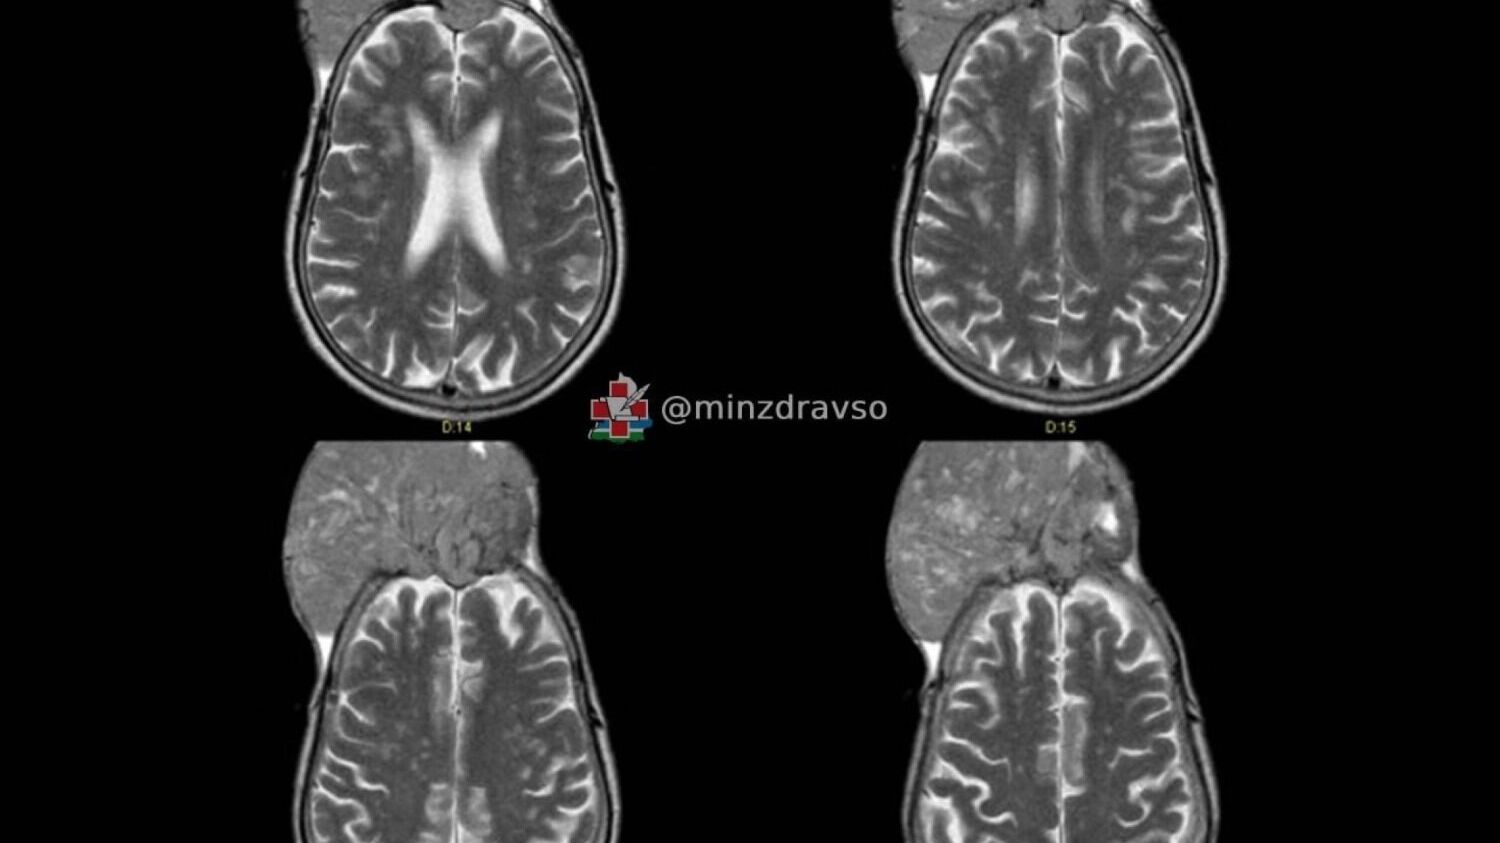

Оказалось, что это менингиома — доброкачественное, но чрезвычайно опасное из-за своих размеров новообразование. На его долю приходится порядка 30% всех опухолей головного мозга.

Операция проходила в два этапа. Сначала врачи перекрыли кровоснабжение опухоли, чтобы избежать сильной кровопотери. Затем за семь часов полностью удалили менингиому, восстановили оболочку мозга и заменили повреждённый участок черепа титановой сеткой. В довершение хирурги убрали рубцы, из-за которых у пациента была залысина, вернув ему нормальный внешний вид.